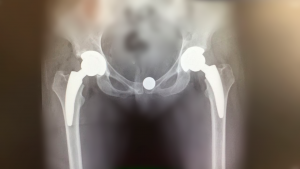

Sin antecedentes en la Argentina, la técnica “fast track” permite acelerar la recuperación kinesiológica, bajar el dolor, mejorar la movilidad y reducir los tiempos de internación. Federico Burgo, médico del Hospital Austral, explica los beneficios del programa que ya se realiza en cirugías de cadera.

Un programa multidisciplinario (clínicos, anestesistas, nutricionistas, hematólogos y kinesiólogos), que abarca diferentes variables, posibilita hacer cirugías de recuperación acelerada, también conocidas como fast track, de reemplazo de cadera. “El programa abarca desde el preoperatorio hasta el postoperatorio, cuyo objetivo final es disminuir el stress operatorio”, explicó el Dr. Federico Burgo, médico del staff de Ortopedia y Traumatología y subjefe de Cirugía reconstructiva de cadera del Hospital Universitario Austral.